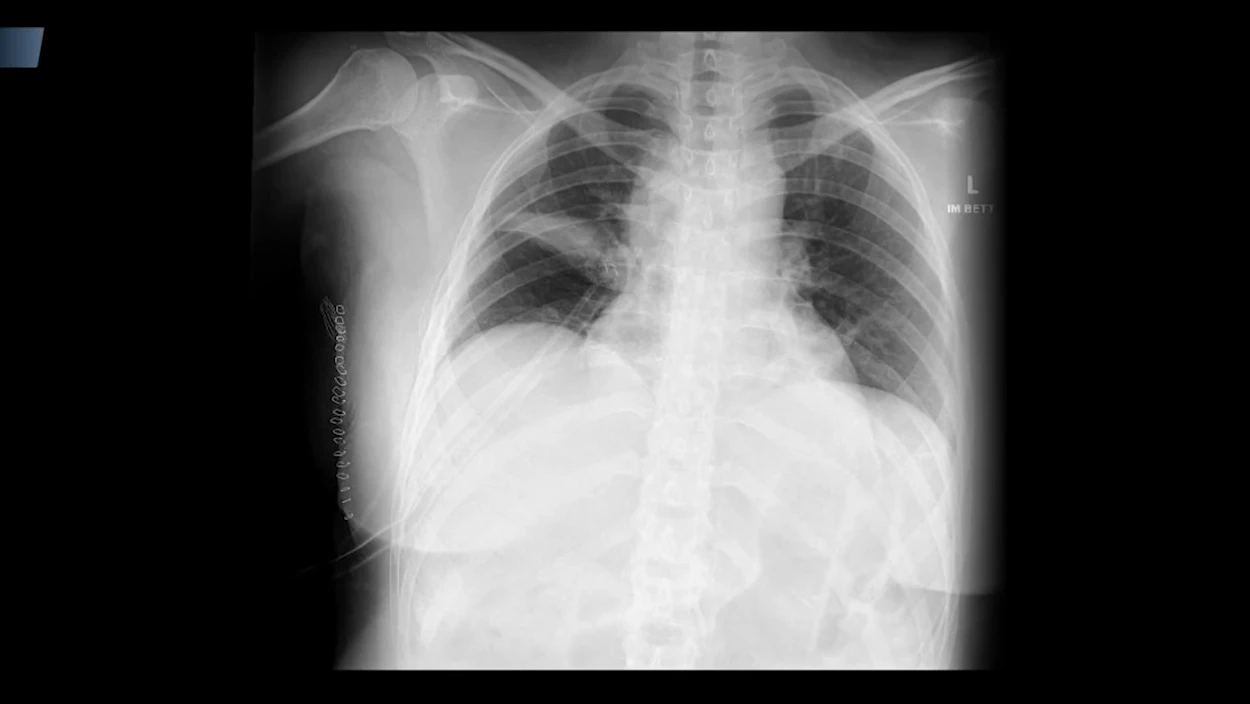

Einer Frau wird in der Steiermark ein Teil der Lunge entfernt. Die Diagnose: Ein bösartiger Tumor - doch die 48-Jährige hat gar keinen Krebs. Anwältin Karin Prutsch fordert daher jetzt eine Entschädigung für ihre Mandantin. Ein Fall, der an jene fatale Fehldiagnose erinnert, die jüngst ganz Österreich erschütterte: Einer 30-jährigen gesunden Frau wurde die Gebärmutter entfernt. Immer wieder gibt es in heimischen Spitälern solche falschen Diagnosen - mit schrecklichen Folgen für die Betroffenen.